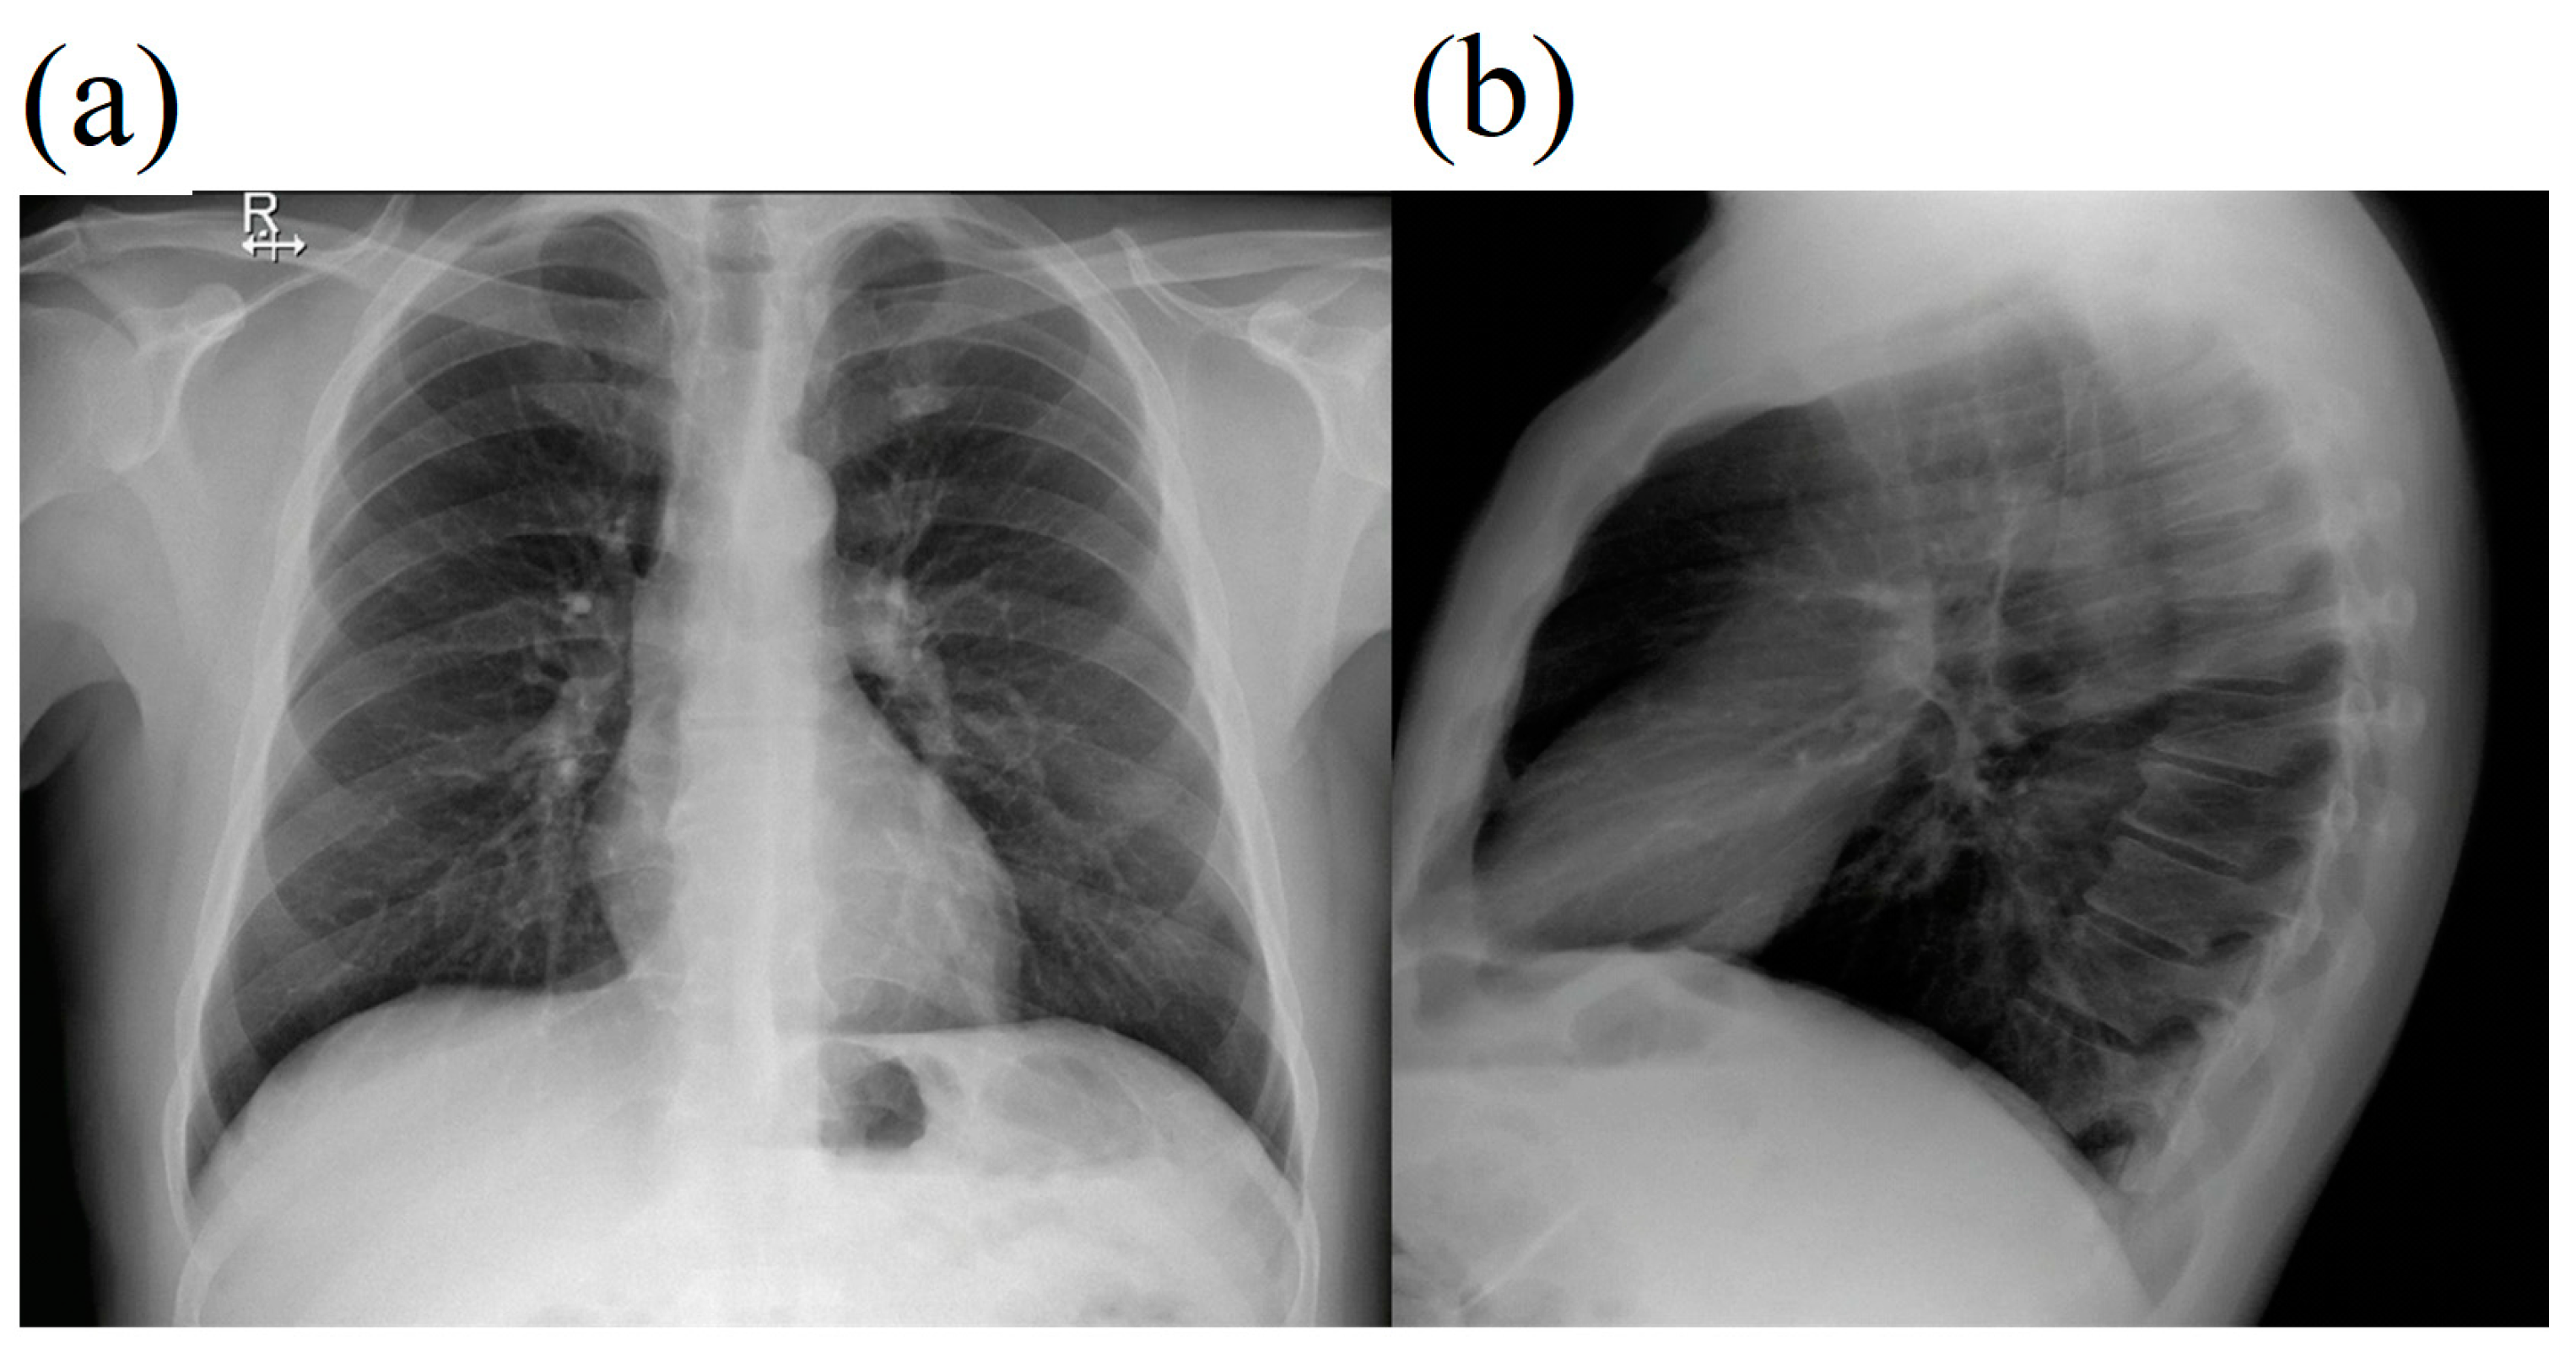

2. Case Report